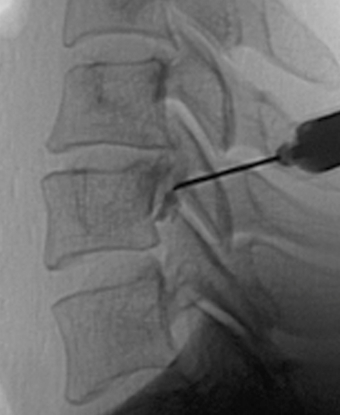

신경주사 치료